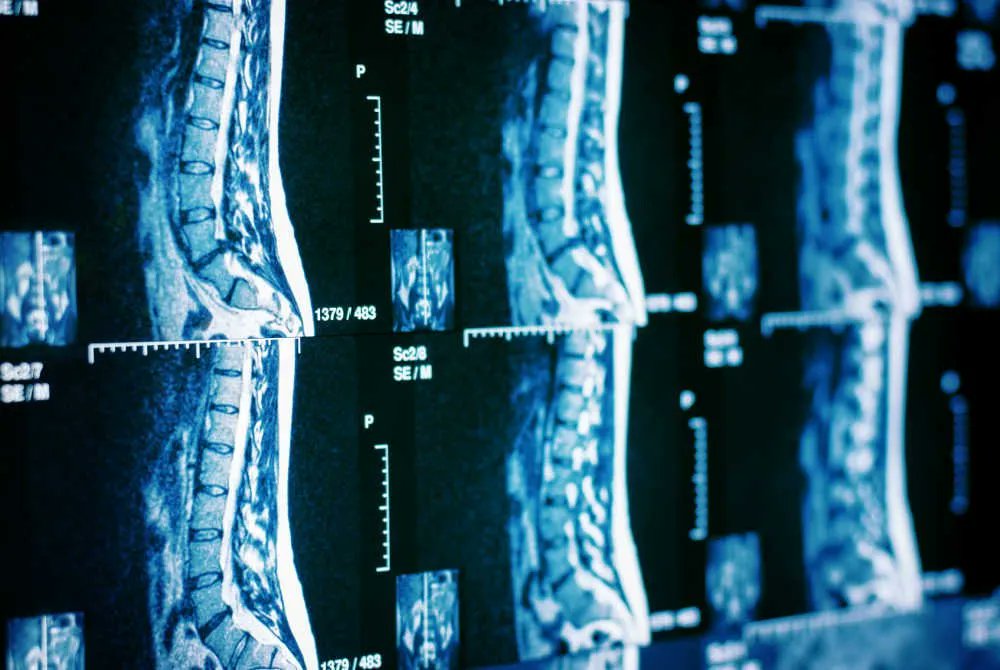

spinal cord injury research x web3 ⚡Radiology NFTs 🧠 🦴 collect NFTs to fund neuroRecovery research 🔬#paralysis #neuroscience #blockchain #nft #deSci #web3